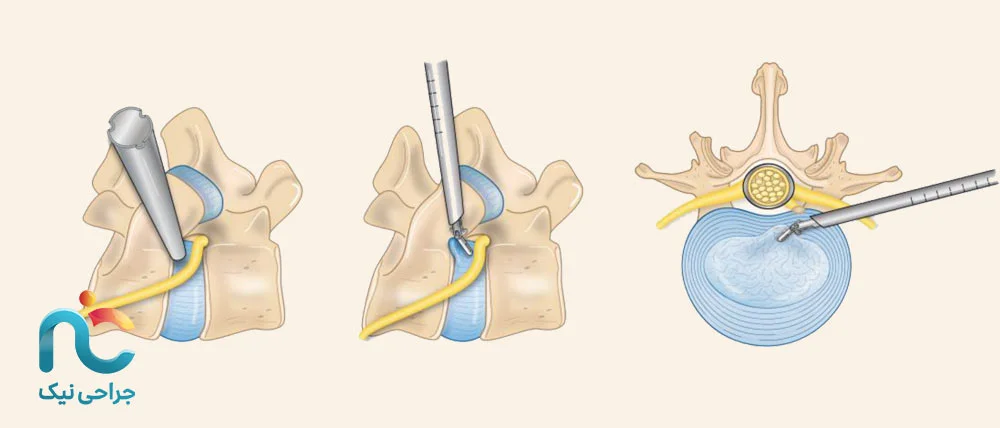

۳. روش ترانسفورامینال (Transforaminal Approach)

این روش جدیدتر و ظریفتر است. در آن، جراح از مسیر بین مهرهها و از کنار وارد میشود؛ جایی که اعصاب از آن عبور میکنند. این تکنیک مخصوص مواردی است که دیسک فقط بخشی از عصب را درگیر کرده و نیاز به دقت بالا دارد. با این روش میتوان بدون جابهجایی زیاد عضلات یا استخوان، فشار را مستقیماً از روی عصب برداشت.

در جراحی اندوسکوپیک دیسک گردن، برخلاف تصور بسیاری از بیماران، هدف این نیست که کل دیسک از بدن خارج شود. در واقع، پزشک تنها بخش فتقکرده یا همان قسمت بیرونزدهی دیسک را که روی عصب فشار میآورد، با ابزارهای ظریف و از طریق یک دوربین مخصوص خارج میکند. این بخش همان جایی است که باعث درد، گزگز یا بیحسی میشود. قسمتهای سالم دیسک که هنوز انعطاف و عملکرد خود را دارند، تا جای ممکن حفظ میشوند تا گردن بتواند حرکت طبیعی خود را بعد از عمل حفظ کند. به همین دلیل است که پس از جراحی، بیمار هنوز بین مهرهها دیسک دارد، فقط دیگر آن فشار آزاردهنده روی عصب وجود ندارد.